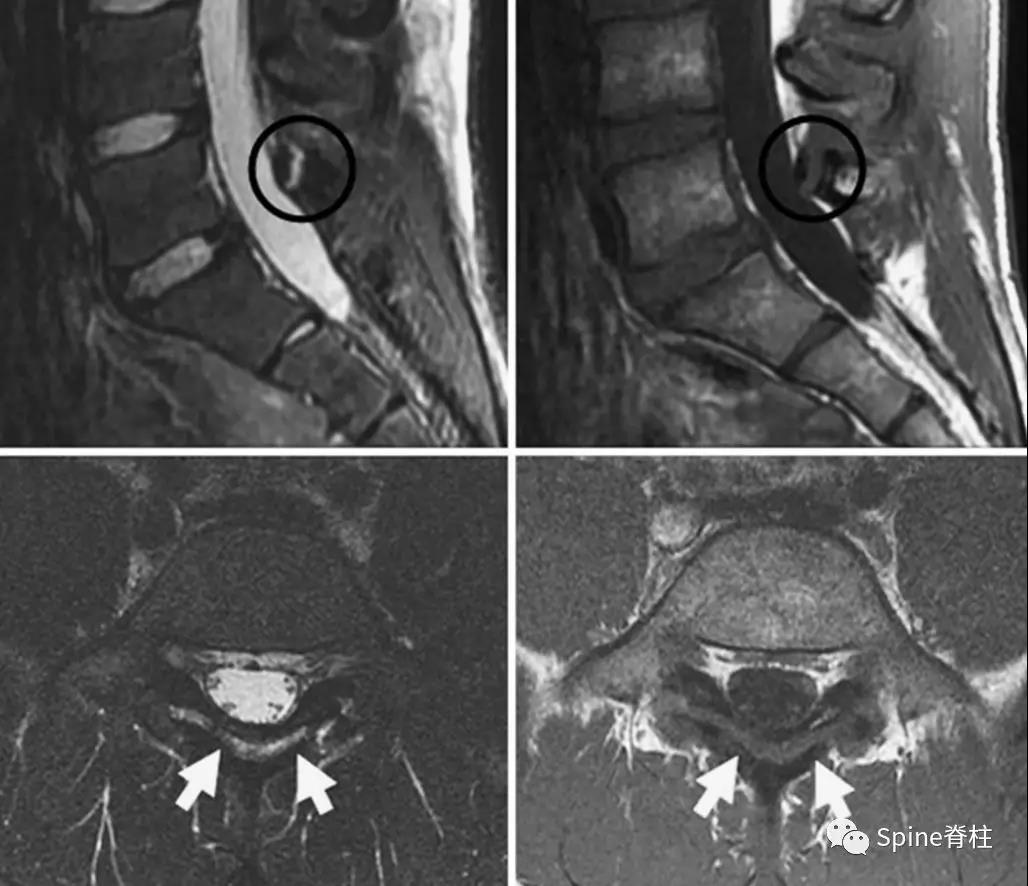

1. 椎弓根裂典型病例

图:15岁腰痛男孩,左侧腰5椎弓根裂A:T1左侧腰5椎弓根低信号(箭头);B:T2左侧腰5椎弓根高信号(箭头);C:T2轴位左侧腰5椎弓根骨折线明显,伴高信号区(箭头)